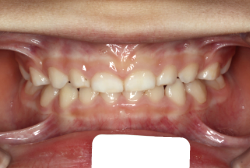

過蓋咬合

過蓋(かがい)咬合とは、奥歯を閉じた時に前歯が深く咬み込み、下の前歯がほとんど見えなくなるくらい閉じすぎになる症状です。強く咬んでいると言うことは、力が強く出て一見良さそうに聞こえますが、深く咬みすぎることは歯にも良くないですし、口腔周囲の環境としても好ましくない状態です。

深く咬みすぎると、歯と歯で接触しながら閉じる距離と面積が広範囲にわたりすぎ、必要以上に歯をすり減らします。また顎の関節の自由な動きを歯と歯の接触関係が必要以上に規制してしまうため、顎の関節の動きがだんだん悪くなり、顎が開きにくくなったり、開いていく途中で大きな音が出たり、ひどいときには途中からそれ以上開けなくなったりします。こういう症状を"顎関節症"と言いますが、こういう状態にもっともなり易い咬み合わせです。顎関節症は、中年期以上にある日突然症状が発現することが多く、一度発症するとなかなか健康な状態にならない、消耗性の病気です。若くて抵抗力のあるうちはまだ良いのですが、過蓋咬合の人は歯がすり減りやすく、時間の経過とともに、ますます咬み合わせが深くなっていく傾向があり、早期発見・早期治療が望まれます。

「歯並びの凸凹を直したい」という主訴で来院したケースです。診断の結果、たしかに「叢生」という隙間が足りないと言うことが原因の凸凹症例でした。

しかし、それ以上に問題なのは「前歯の噛み合い方が深すぎる」という症状で、初診の歯の正面写真を見ると下の前歯が全く見えません。こういう症状を矯正学では「過蓋咬合(かがいこうごう)」と言います。過蓋咬合を放置すると、将来的に顎関節に悪影響を与えるとされており、顎関節症の原因因子の一つです。また下の前歯の先端が、上の前歯の裏側の歯茎と強く接触するため、歯周病の原因にもなります。

検査の結果、凸凹が軽症なため非抜歯で矯正すること可能と判断、マルチブラケット装置にて治療しました。治療後は歯並びが綺麗になっただけでなく、噛み合わせ的にも正しい状態が確立しています。